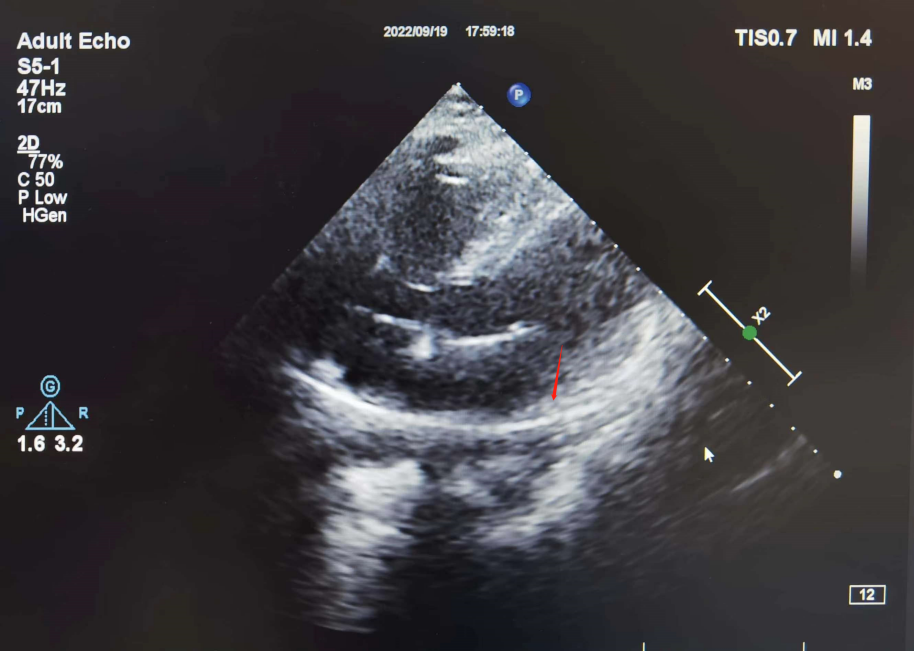

彩超下观察心室电极导线的位置

心室电极放置:在超声引导下,心室电极经上腔静脉后顺利进入右心房,跨越三尖瓣,顺利到达右室心尖部,经过起搏测试,起搏参数良好,但起搏时QRS波形明显增宽,考虑高心尖部起搏比例可能导致心功能下降,手术团队追求精益求精,多次调整起搏器电极位置,最终将起搏电极固定于低位间隔,起搏图形良好、参数良好。超声下观察电极曲度,顺着电极方向观察到电极张力良好。

心室电极测试参数为:阈值:0.4V,R波:15.0mv,阻抗:640Ω。